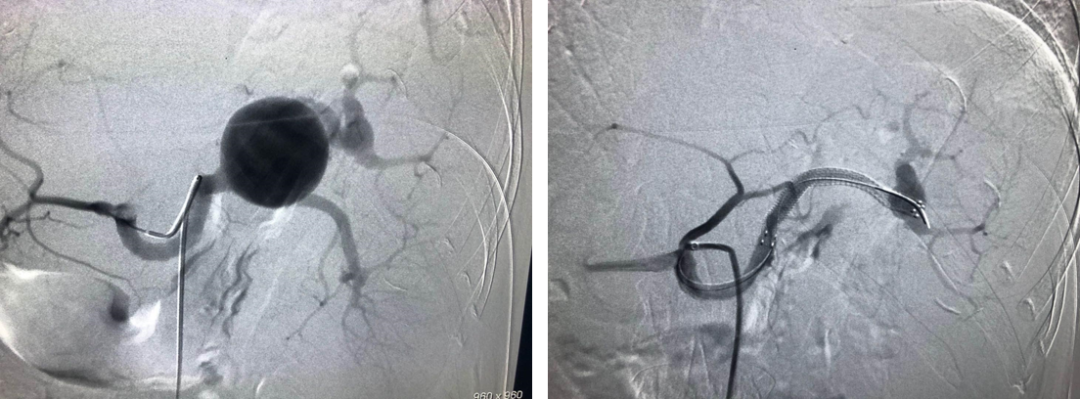

病例8 脾动脉瘤破裂直接栓塞